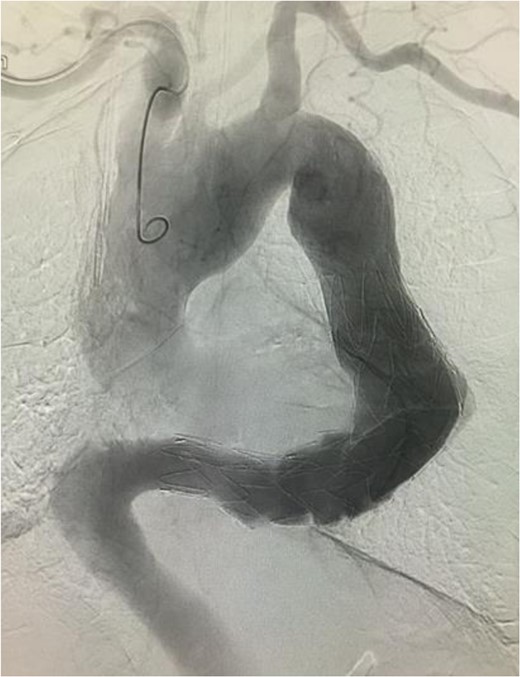

Angiographic image at the completion of treatment. No endoleak was observed. There was no contrast enhancement in the location of the aneurysm.